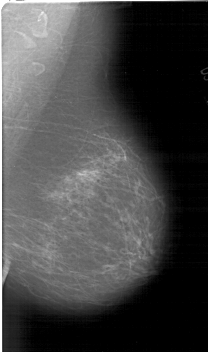

A_1549_1.LEFT_MLO

LEFT_MLO LINES 6646 PIXELS_PER_LINE 3631 BITS_PER_PIXEL 12 RESOLUTION 43.5 OVERLAY